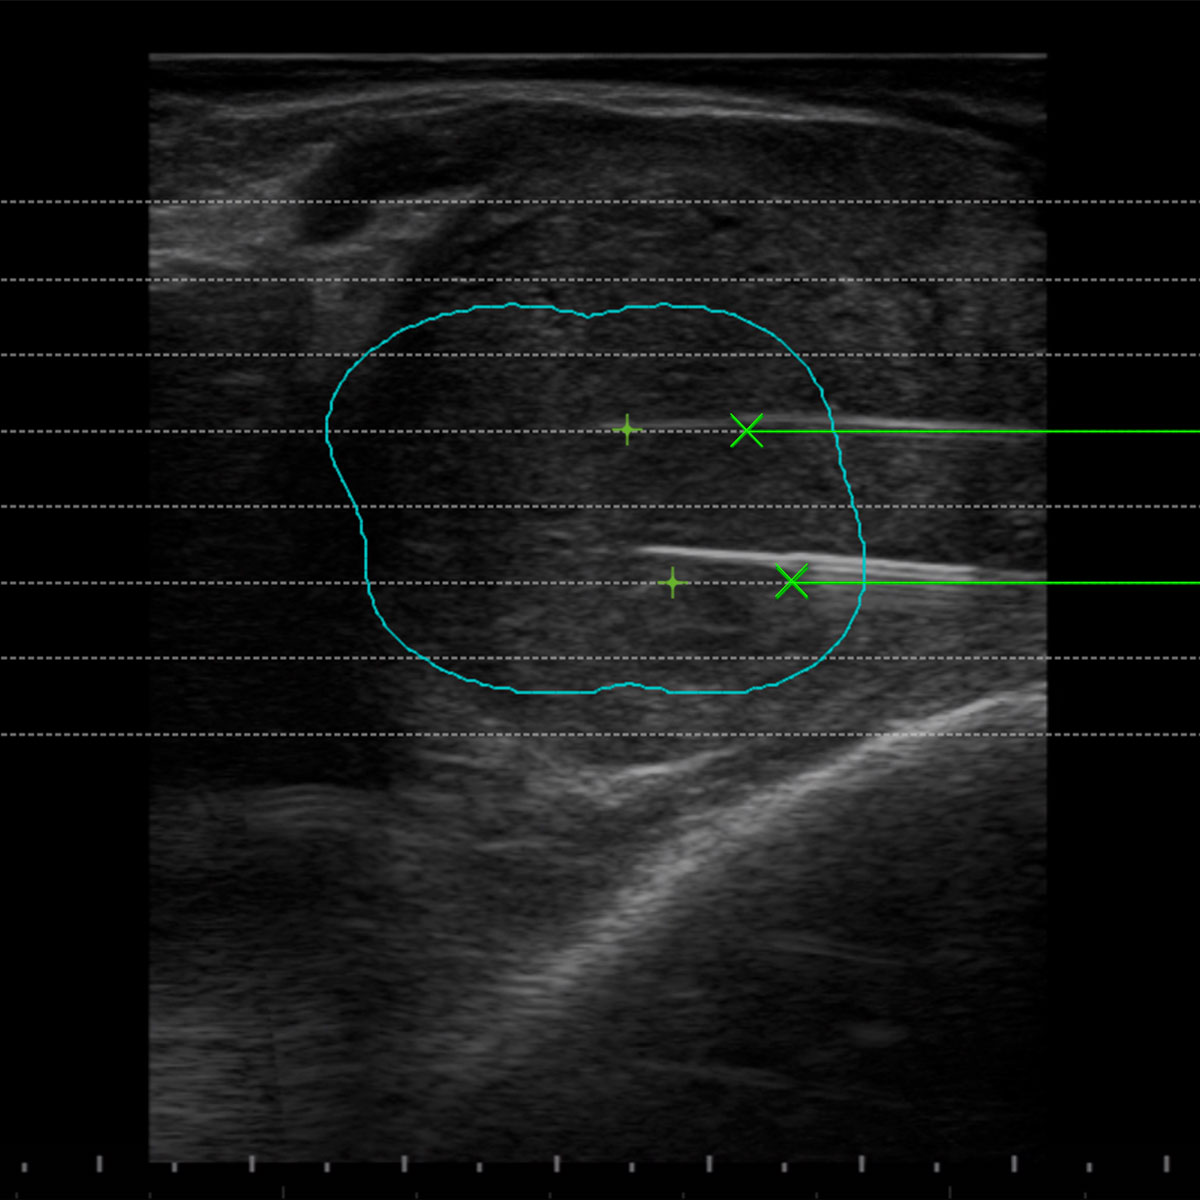

Sistemi Guida degli applicatori e Software Biopsia dedicati

I Sistemi Guida sulle sonde Esaote sono stati sviluppati per ciascuna applicazione per facilitare l’operatore nel posizionamento di più fibre all’interno della lesione da trattare. I Software Biopsia dedicati alla Termoablazione con EchoLaser nella unità US visualizzano le linee guida sullo schermo per ogni differente guida al fine di valutare il miglior posizionamento dell’applicatore in riferimento alla dimensione, morfologia e posizione della lesione.

Il Software di Pianificazione consente all’operatore di valutare la traiettoria di inserimento degli aghi introduttori e l’opzione di trattamento adeguata (numero di applicatori, numero di pull-back, distanza degli applicatori) per ogni caso specifico.

In senso orario:

4. Software di pianificazione pre-trattamento per l’applicazione sulla prostata